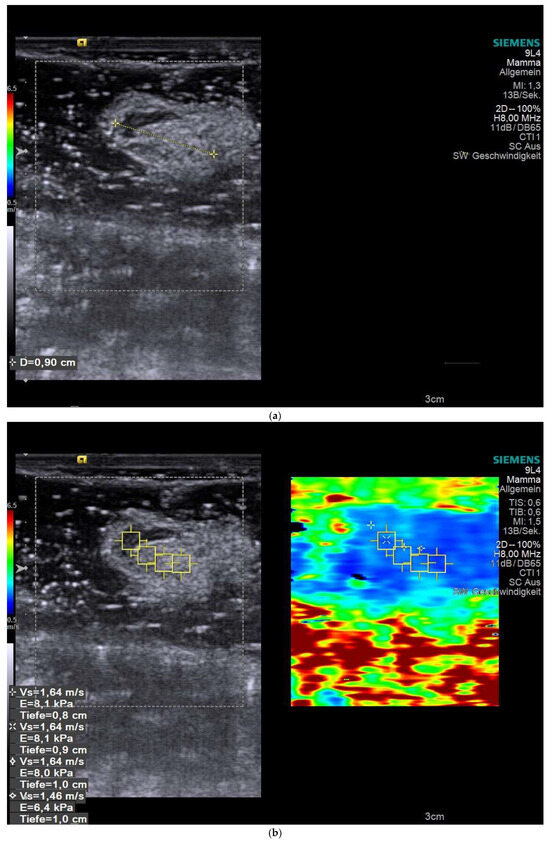

Figure 1 illustrates an ex vivo SWE assessment of a SLN. Figure 1a shows a single SLN submerged in coupling gel with measurement of its long-axis diameter. Figure 1b shows Cortical ROIs, delineated on the corresponding B-mode ultrasound image, demonstrate shear-wave velocities.

Figure 1.

Representative SWE measurement of a SLN. (a) B-mode ultrasound image illustrates a single SLN submerged in coupling gel with measurement its long-axis diameter. (b) Image of the sentinel node with SWE measurements, indicating the precise locations at which SW velocities were measured.